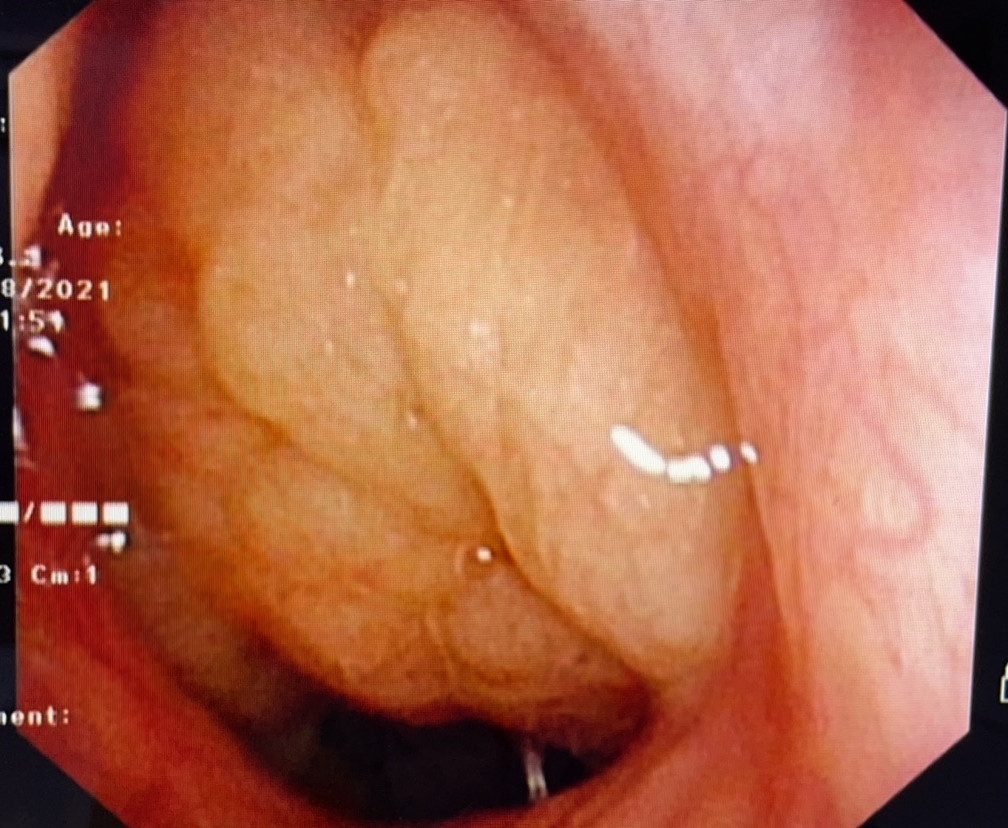

主要原因是呼吸不通畅。儿童时期易患上呼吸道感染(如急性鼻炎、急性扁桃体炎等)、过敏性疾病(如过敏性鼻炎),若反复发作,腺样体可迅速增生肥大,阻塞后鼻孔、加重鼻阻塞、阻碍鼻腔引流,鼻炎鼻窦炎分泌物又会刺激腺样体,使之继续增生,形成互为因果的恶性循环。肿大的腺样体堵住呼吸要道,孩子只能张嘴呼吸,久而久之就会形成上面所说的“腺样体面容”。

腺样体肥大除了影响面容,还可能导致支气管炎,造成儿童精神不振、反应迟钝,影响孩子生长发育。治疗上有药物治疗和手术治疗,但医生会根据具体病情来选择治疗方法。如果孩子没有鼻塞,但睡眠时出现打鼾、张口呼吸、呼吸暂停、听力异常等症状,可先不治疗,注意增加孩子抵抗力,避免其反复出现上呼吸道感染,动态观察即可。对于保守治疗腺样体、扁桃体肥大效果不明显的,可以通过手术解决。